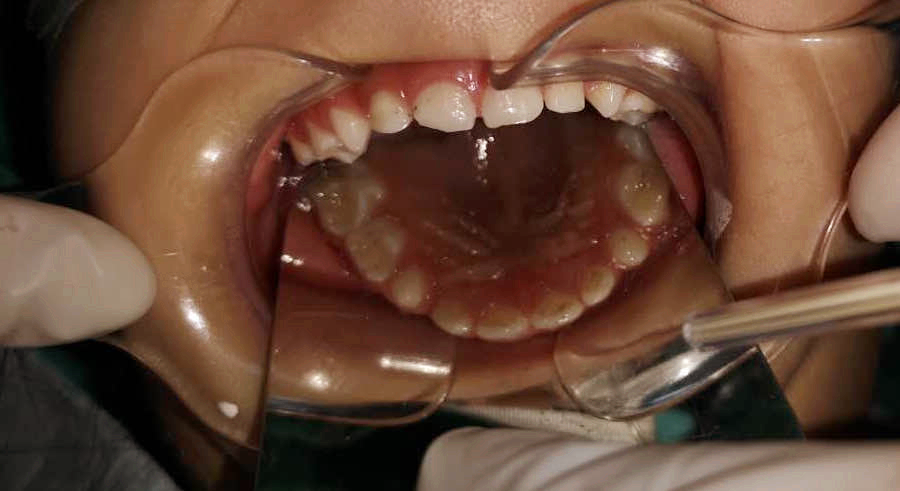

調(diào)節(jié)后

齲齒充填、根管調(diào)節(jié)、窩溝封閉......西海岸新區(qū)中心醫(yī)院的兒童口腔醫(yī)生丁彬主治醫(yī)師和申家麗住院醫(yī)師有條不紊地進(jìn)行著操作,劉亞芳醫(yī)師、李雪飛醫(yī)師和高聰醫(yī)師在旁邊配合著操作,一切井然有序,只有儀器發(fā)出“嘀、嘀”的聲音,提醒著時(shí)間的流逝。

丁彬醫(yī)師和申家麗醫(yī)師正在為小患者進(jìn)行全麻下牙齒調(diào)節(jié)

兩個(gè)多小時(shí)后,這一多達(dá)8顆患牙的復(fù)雜調(diào)節(jié)順利完成。在這期間,鑫鑫的心率和血壓一直被密切監(jiān)測(cè)著,一切都很正常。